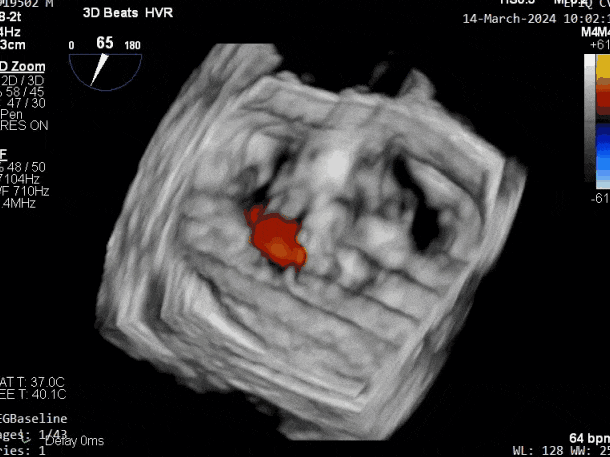

释放瓣膜夹后评估,二尖瓣呈双孔,外侧仍有残余反流

第二个瓣膜夹释放后评估,二尖瓣呈双孔,外侧仍有残余反流

第三个瓣膜夹释放后评估,释放后评估,二尖瓣呈双孔,组织桥张力合适,瓣膜夹轴向与二尖瓣闭合线垂直,无残余反流